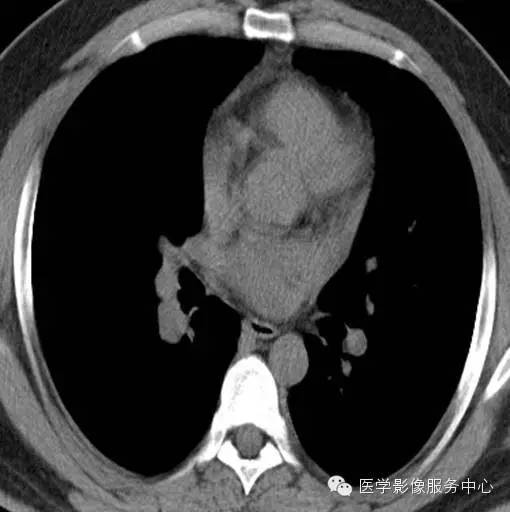

男, 26岁,因“咯血二十余日”入院 。患者一年余前无明显诱因下咯血,鲜红色,自诉无其他不适,至当地医院治疗后缓解,二十余日前无明显诱因下咯血,鲜红色,自诉无伴随症状。

2012年12月3号

影像分析:右侧肺门处见小团块状密度增高影,密度尚均匀,边缘毛糙,增强扫描病灶不均匀强化。

病理:肺神经内分泌瘤